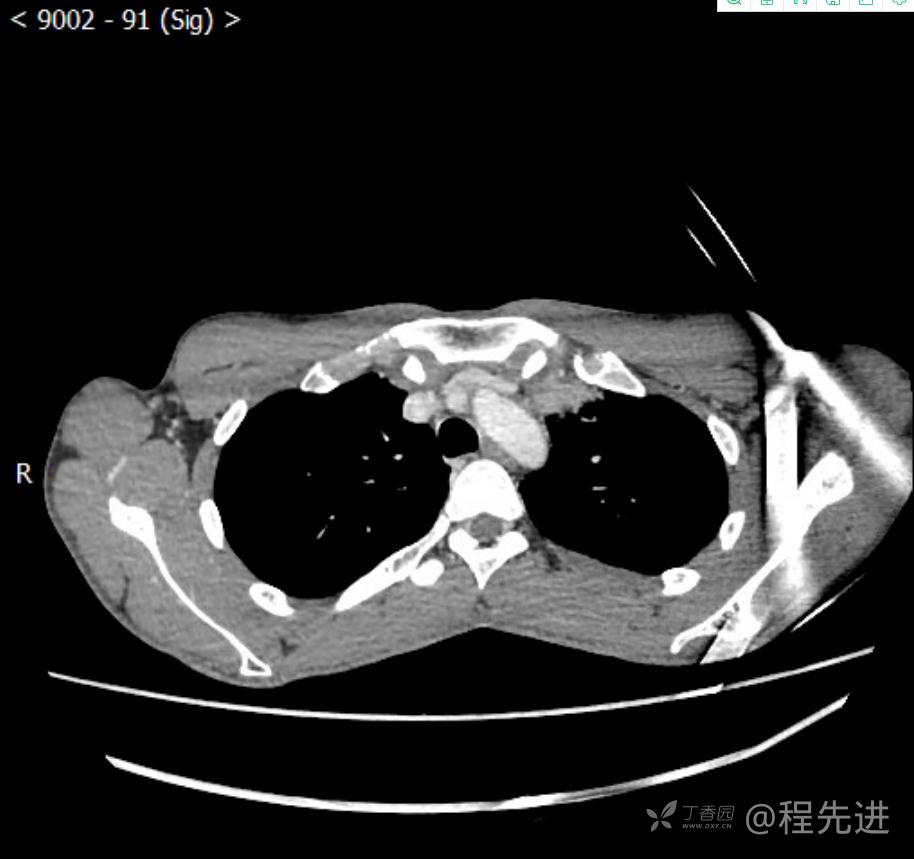

主诉:反复咳嗽1月,发现“纵隔”占位半月,乏力10余天。

现病史:患者1月前无明显诱因出现咳嗽,以夜间为著,伴有少量白痰,无发热,无胸痛、咯血,无痰中带血,未予重视,半月前外院行胸部CT检查发现“左前上纵隔”占位,未予进一步检查及治疗。近10余天自觉乏力,逐渐加重。